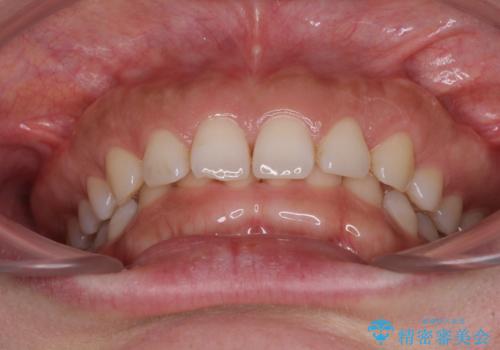

- 顎が疲れるほどのディープバイトを気にして来院された患者様です。

手前に傾斜している奥歯を直立させながら、歯列全体の平面を均一に整えることでディープバイトを改善していくこととしました。

ディープバイトは咬合力が強いことが特徴であり、より良い仕上がりとするために、臼歯部のコントロールを行いやすいワイヤー装置を用いて矯正治療を行うこととしました。